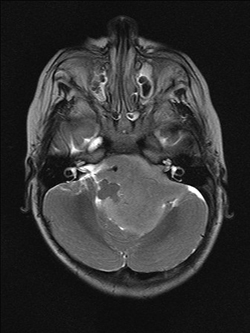

We ended up taking Ethan to the emergency room at a children’s hospital. After a number of visits, he was admitted for a series of tests. Eventually, the doctors found Ethan’s tumor during an MRI scan under general anesthetic. His tumor was wrapped around his brain stem in the posterior fossa, about 6cm by 7cm – the size of a fist. That was in January 2012.

When the brain tumor was first located, it was so large that it blocked the flow of cerebrospinal fluid in Ethan’s head and spine. This resulted in build-up and the pressure was slowly squeezing his brain against the inside of his skull, causing him agonizing pain. Surgeons inserted an external ventricular drain to relieve the pressure. A week later, Ethan endured a marathon nine-hour surgery to remove the tumor. Amazingly, doctors were able to remove approximately 98% of the tumor. We were relieved that Ethan survived the surgery and he was admitted to ICU. Later, pathology results came back with a diagnosis of grade 2 ependymoma.